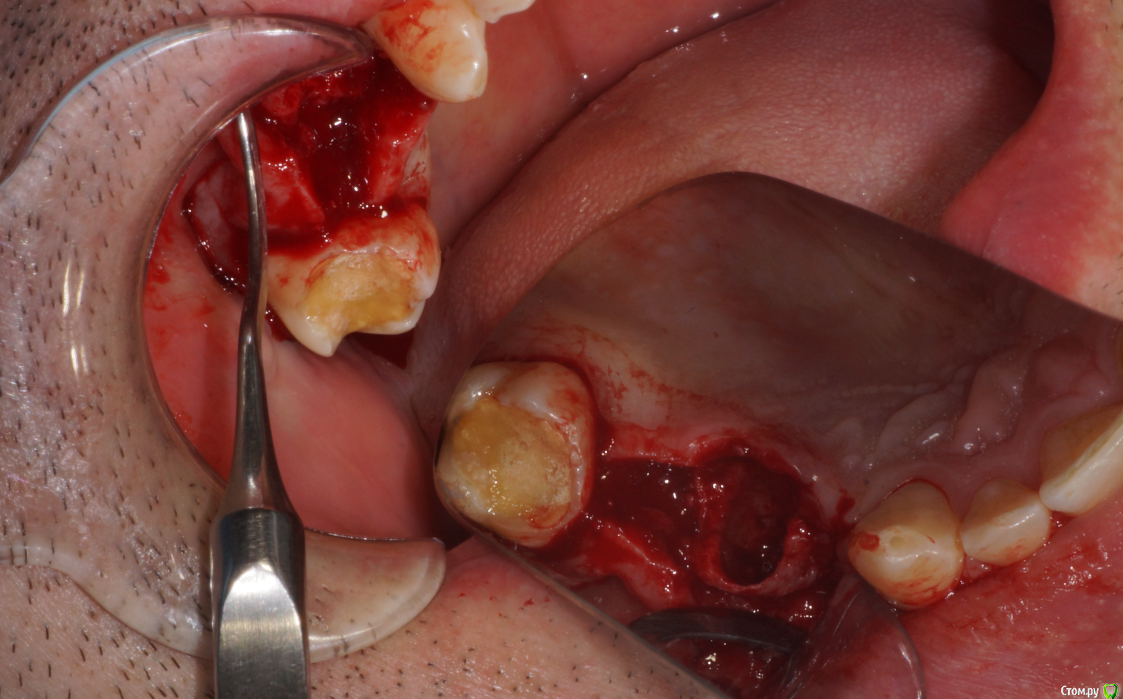

Пришел пациент с вопросом о 1.5. Поговорили о варианте одномоментного всего. Ушел на КТ. Принес такое.

Я сначала решил, что в пазухе новообразование. Посмотрев внимательнее подумал что корень. Оказалось нечто среднее - недоформировавшийся корень, вросший в стенки пазухи.

В день вмешательства обрадовала ассистент - оказывается заказ "открытый синус лифт" еще не предполагает заказа на комплект гладилок. Сетевые клиники такие сетевые. Пришлось дедовским способом - турбинка, серповидная и распатор.